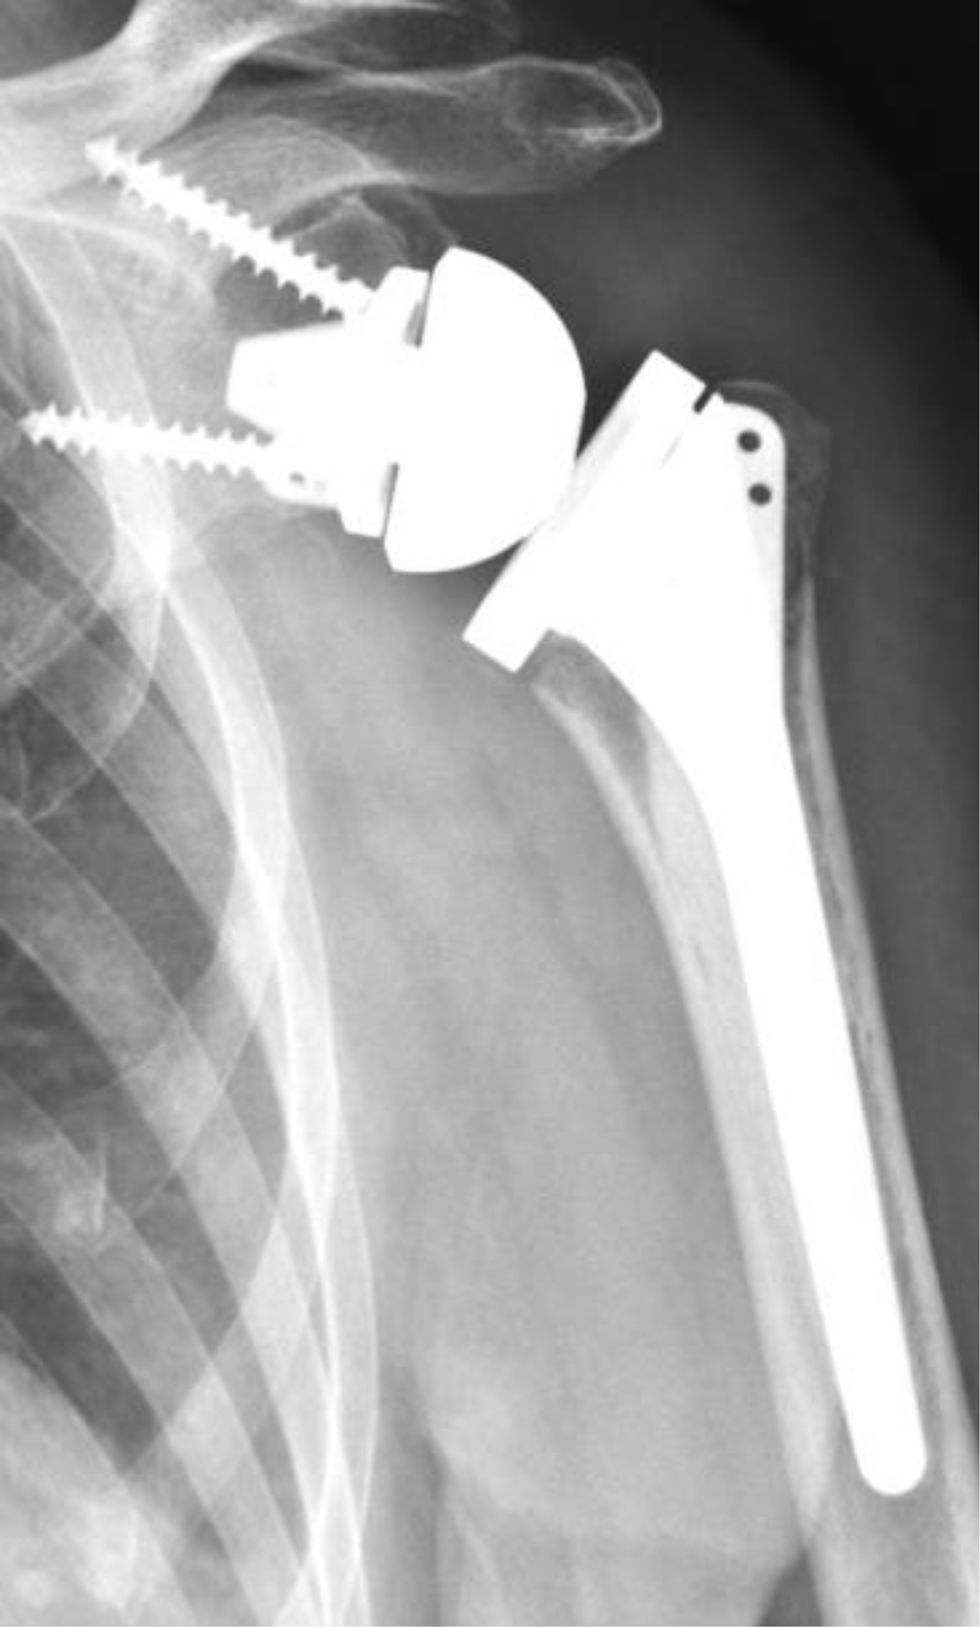

Para la implantación del componente glenoideo se estableció una inclinación inferior de 10°, equivalente a un reverse shoulder angle (RSA) de 0°15. La superficie glenoidea se preparó mediante fresado hasta obtener hueso subcondral seguido de la perforación de un orificio central para la inserción de la quilla (grupo MAL) o poste (grupoL). Se impactó la metaglena y se fijó con tornillos periféricos. En el grupo MAL se colocaron 2 tornillos no bloqueados, y en el grupoL con una metaglena circular se colocaron 4 tornillos: 2 bloqueados y 2 no bloqueados. Posteriormente se colocó la glenoesfera y se fijó con un tornillo central. Se implantó el componente humeral de 135° de forma cementada con una retroversión de 20°, empleando una guía de versión alineada con el antebrazo en flexión, insertando previamente un restrictor de cemento en el canal endomedular. Tras la colocación del inserto se realizó la reducción definitiva de la prótesis, verificando la estabilidad y el rango de movimiento. Para la fijación de las tuberosidades, se fijaron en la cara lateral del vástago buscando una reducción anatómica según la técnica descripta por Boileau (fig. 1), aplicando un cerclaje con 4 suturas horizontales y 2 suturas verticales12.

La consolidación anatómica se definió en la radiografía anteroposterior (AP) con rotación neutra, al observar la tuberosidad mayor a nivel de la cara lateral del vástago humeral, en contacto con la diáfisis y sin sobrepasar el extremo superior del polietileno (fig. 2). Se consideró consolidación no anatómica cuando la tuberosidad no era visible en la radiografía de hombro anteroposterior, pero su consolidación se evidenciaba en la radiografía de perfil o axial, indicando una migración o traslación posterosuperior (fig. 3). Finalmente, se determinó como falla de consolidación la presencia de signos radiográficos de seudoartrosis o lisis en la radiografía anteroposterior de hombro y axial de escápula (fig. 4).